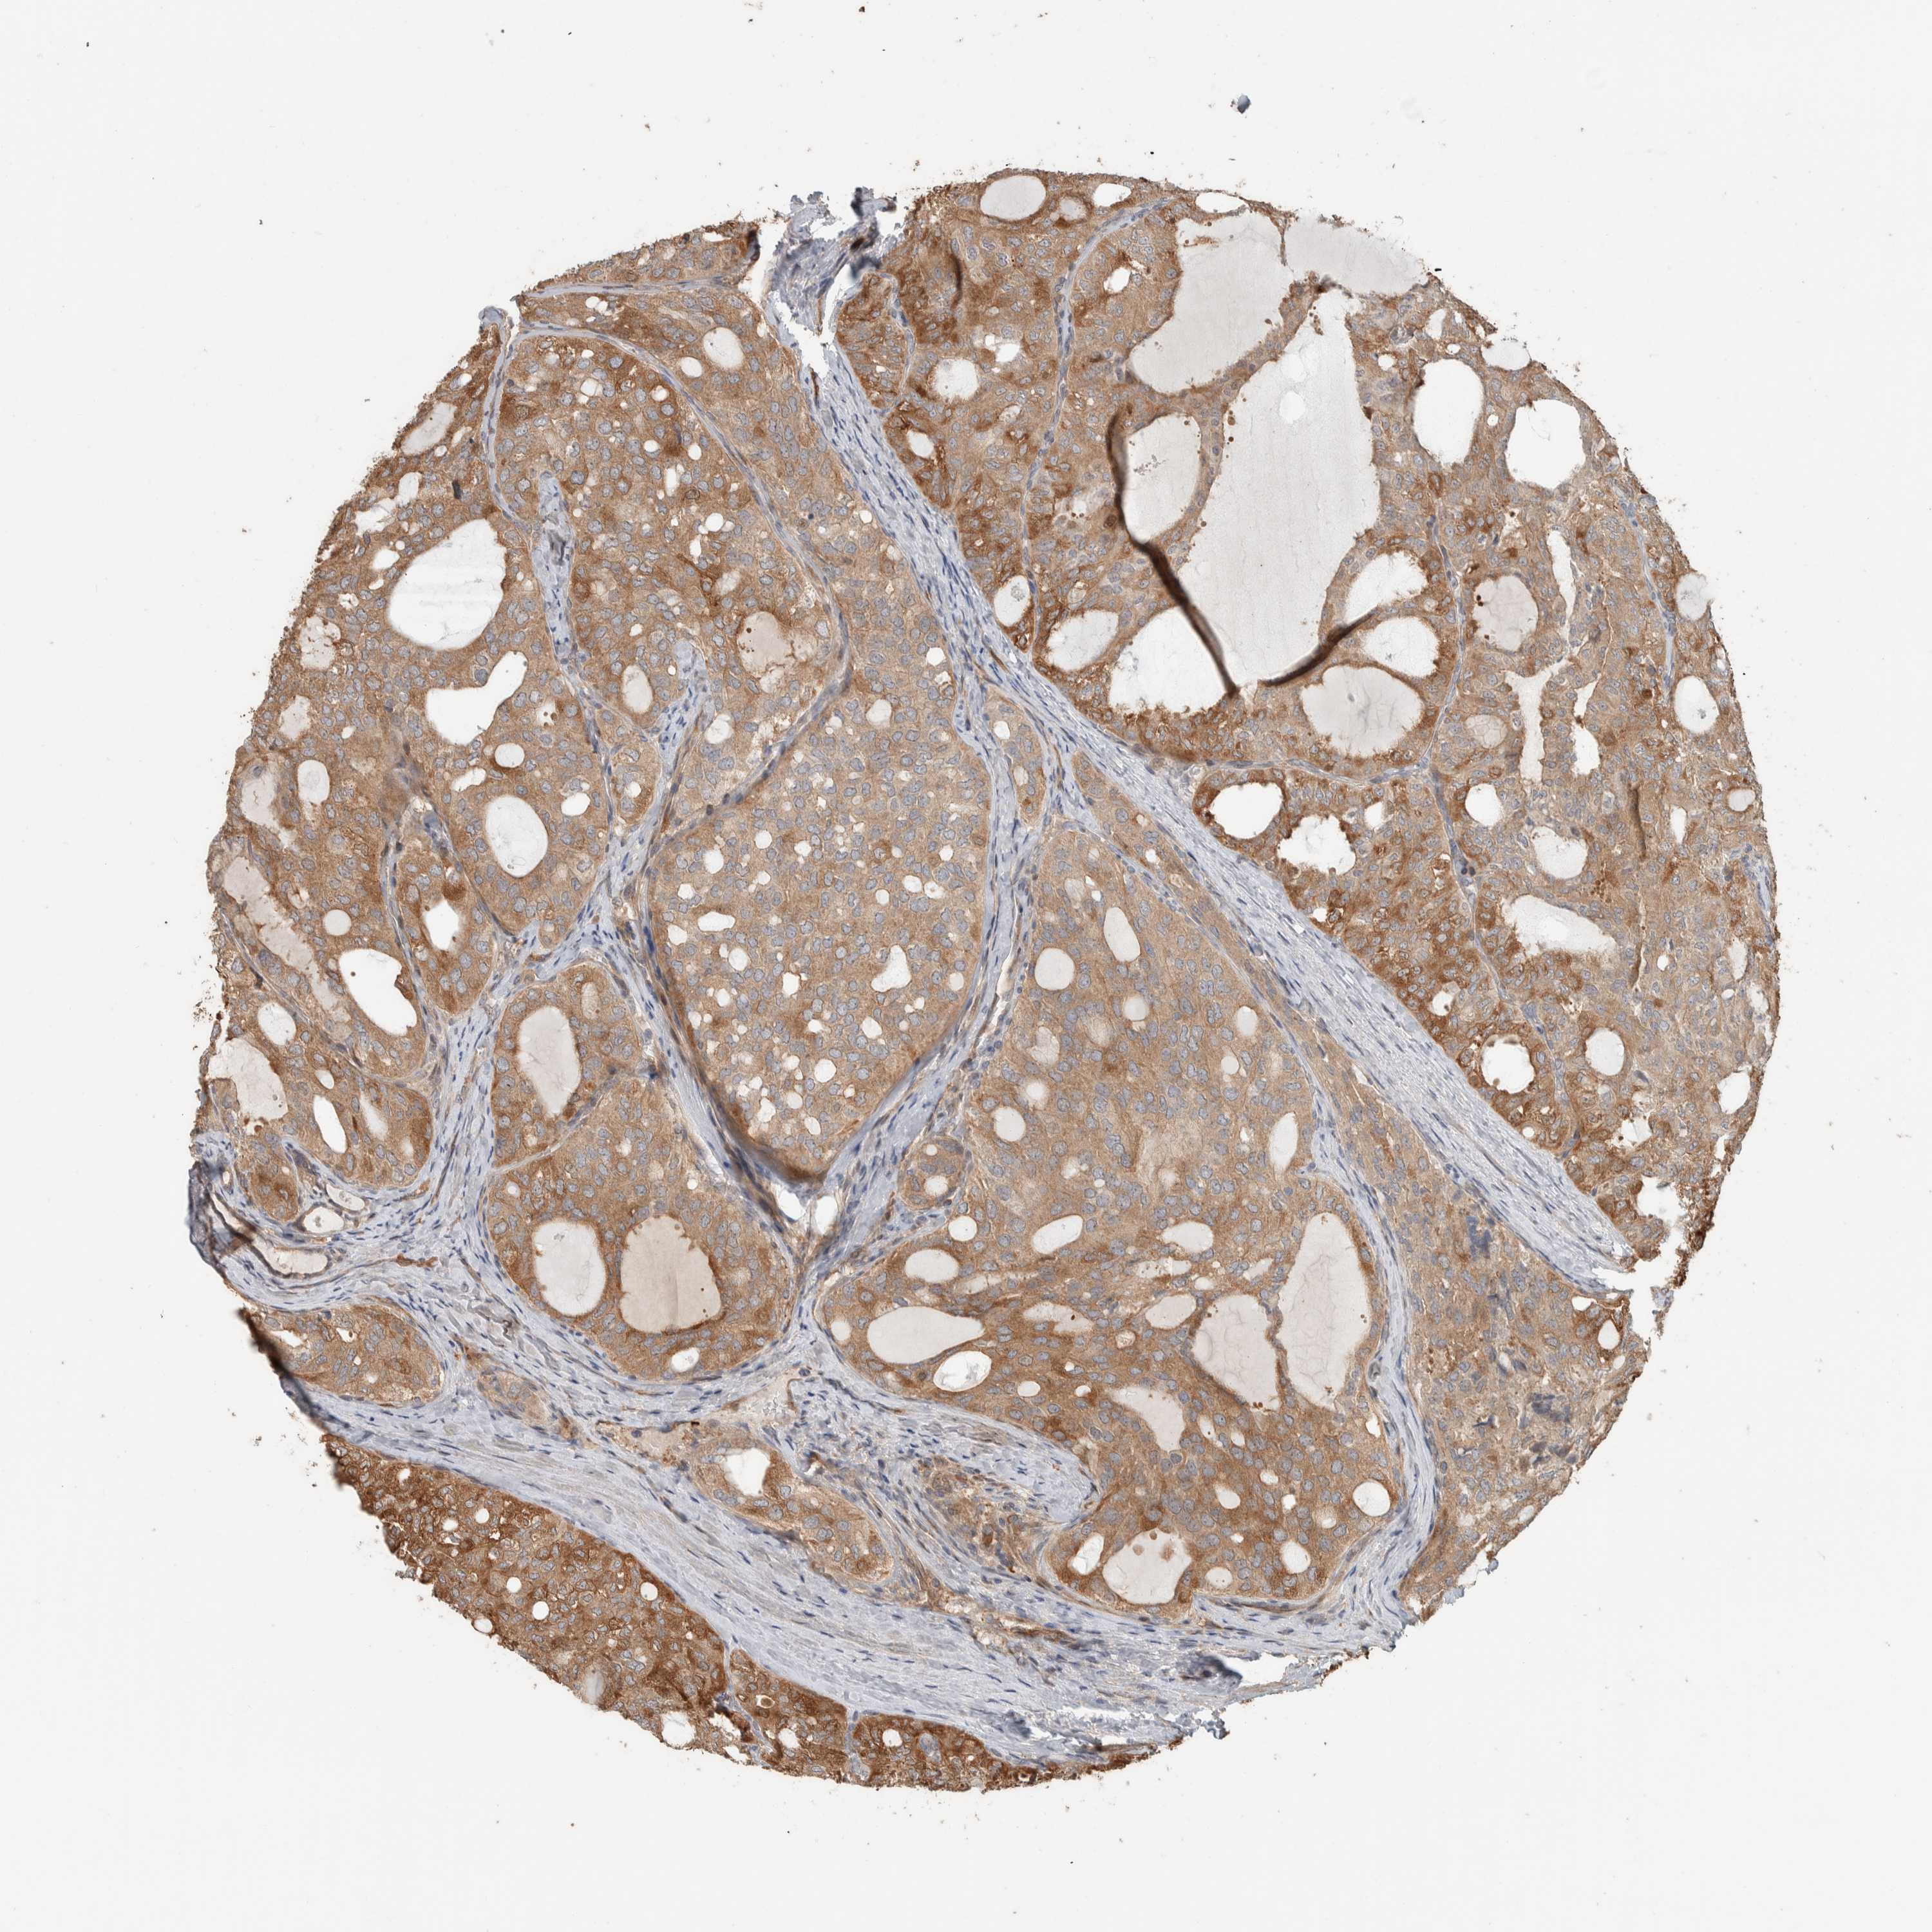

THYROID CANCER - Protein expressioni

A mouse-over function shows sample information and annotation data. Click on an image to view it in a full screen mode. Samples can be filtered based on level of antibody staining by selecting one or several of the following categories: high, medium, low and not detected. The assay and annotation is described here.

Note that samples used for immunohistochemistry by the Human Protein Atlas do not correspond to samples in the TCGA dataset.

Antibody stainingi

Antibody staining in the annotated cell types in the current human tissue is reported as not detected, low, medium, or high, based on conventional immunohistochemistry profiling in selected tissues. This score is based on the combination of the staining intensity and fraction of stained cells.

Each image is clickable and will lead to virtual microscopy that enables deeper exploration of all samples and also displays staining intensity scores, fraction scores and subcellular localization as well as patient and tissue information for each sample.

Antibody HPA023319

Antibody HPA023320

Antibody HPA023321

Antibody HPA023325

Papillary adenocarcinoma, NOS

Follicular adenoma carcinoma, NOS